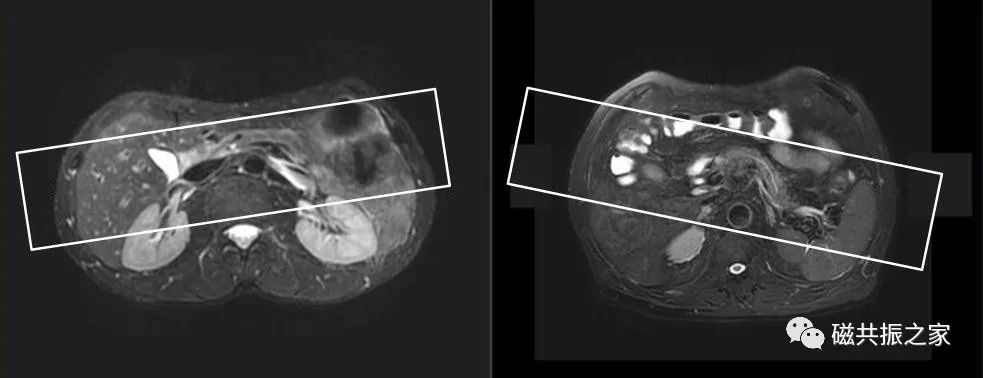

3D MRCP模块扫描范围尽量不要包括前腹部,同时添加相应的饱和带,可以有效的改善前腹部呼吸运动带来的伪影。同时扫描模块能避开主动脉的尽可能避开主动脉区域。